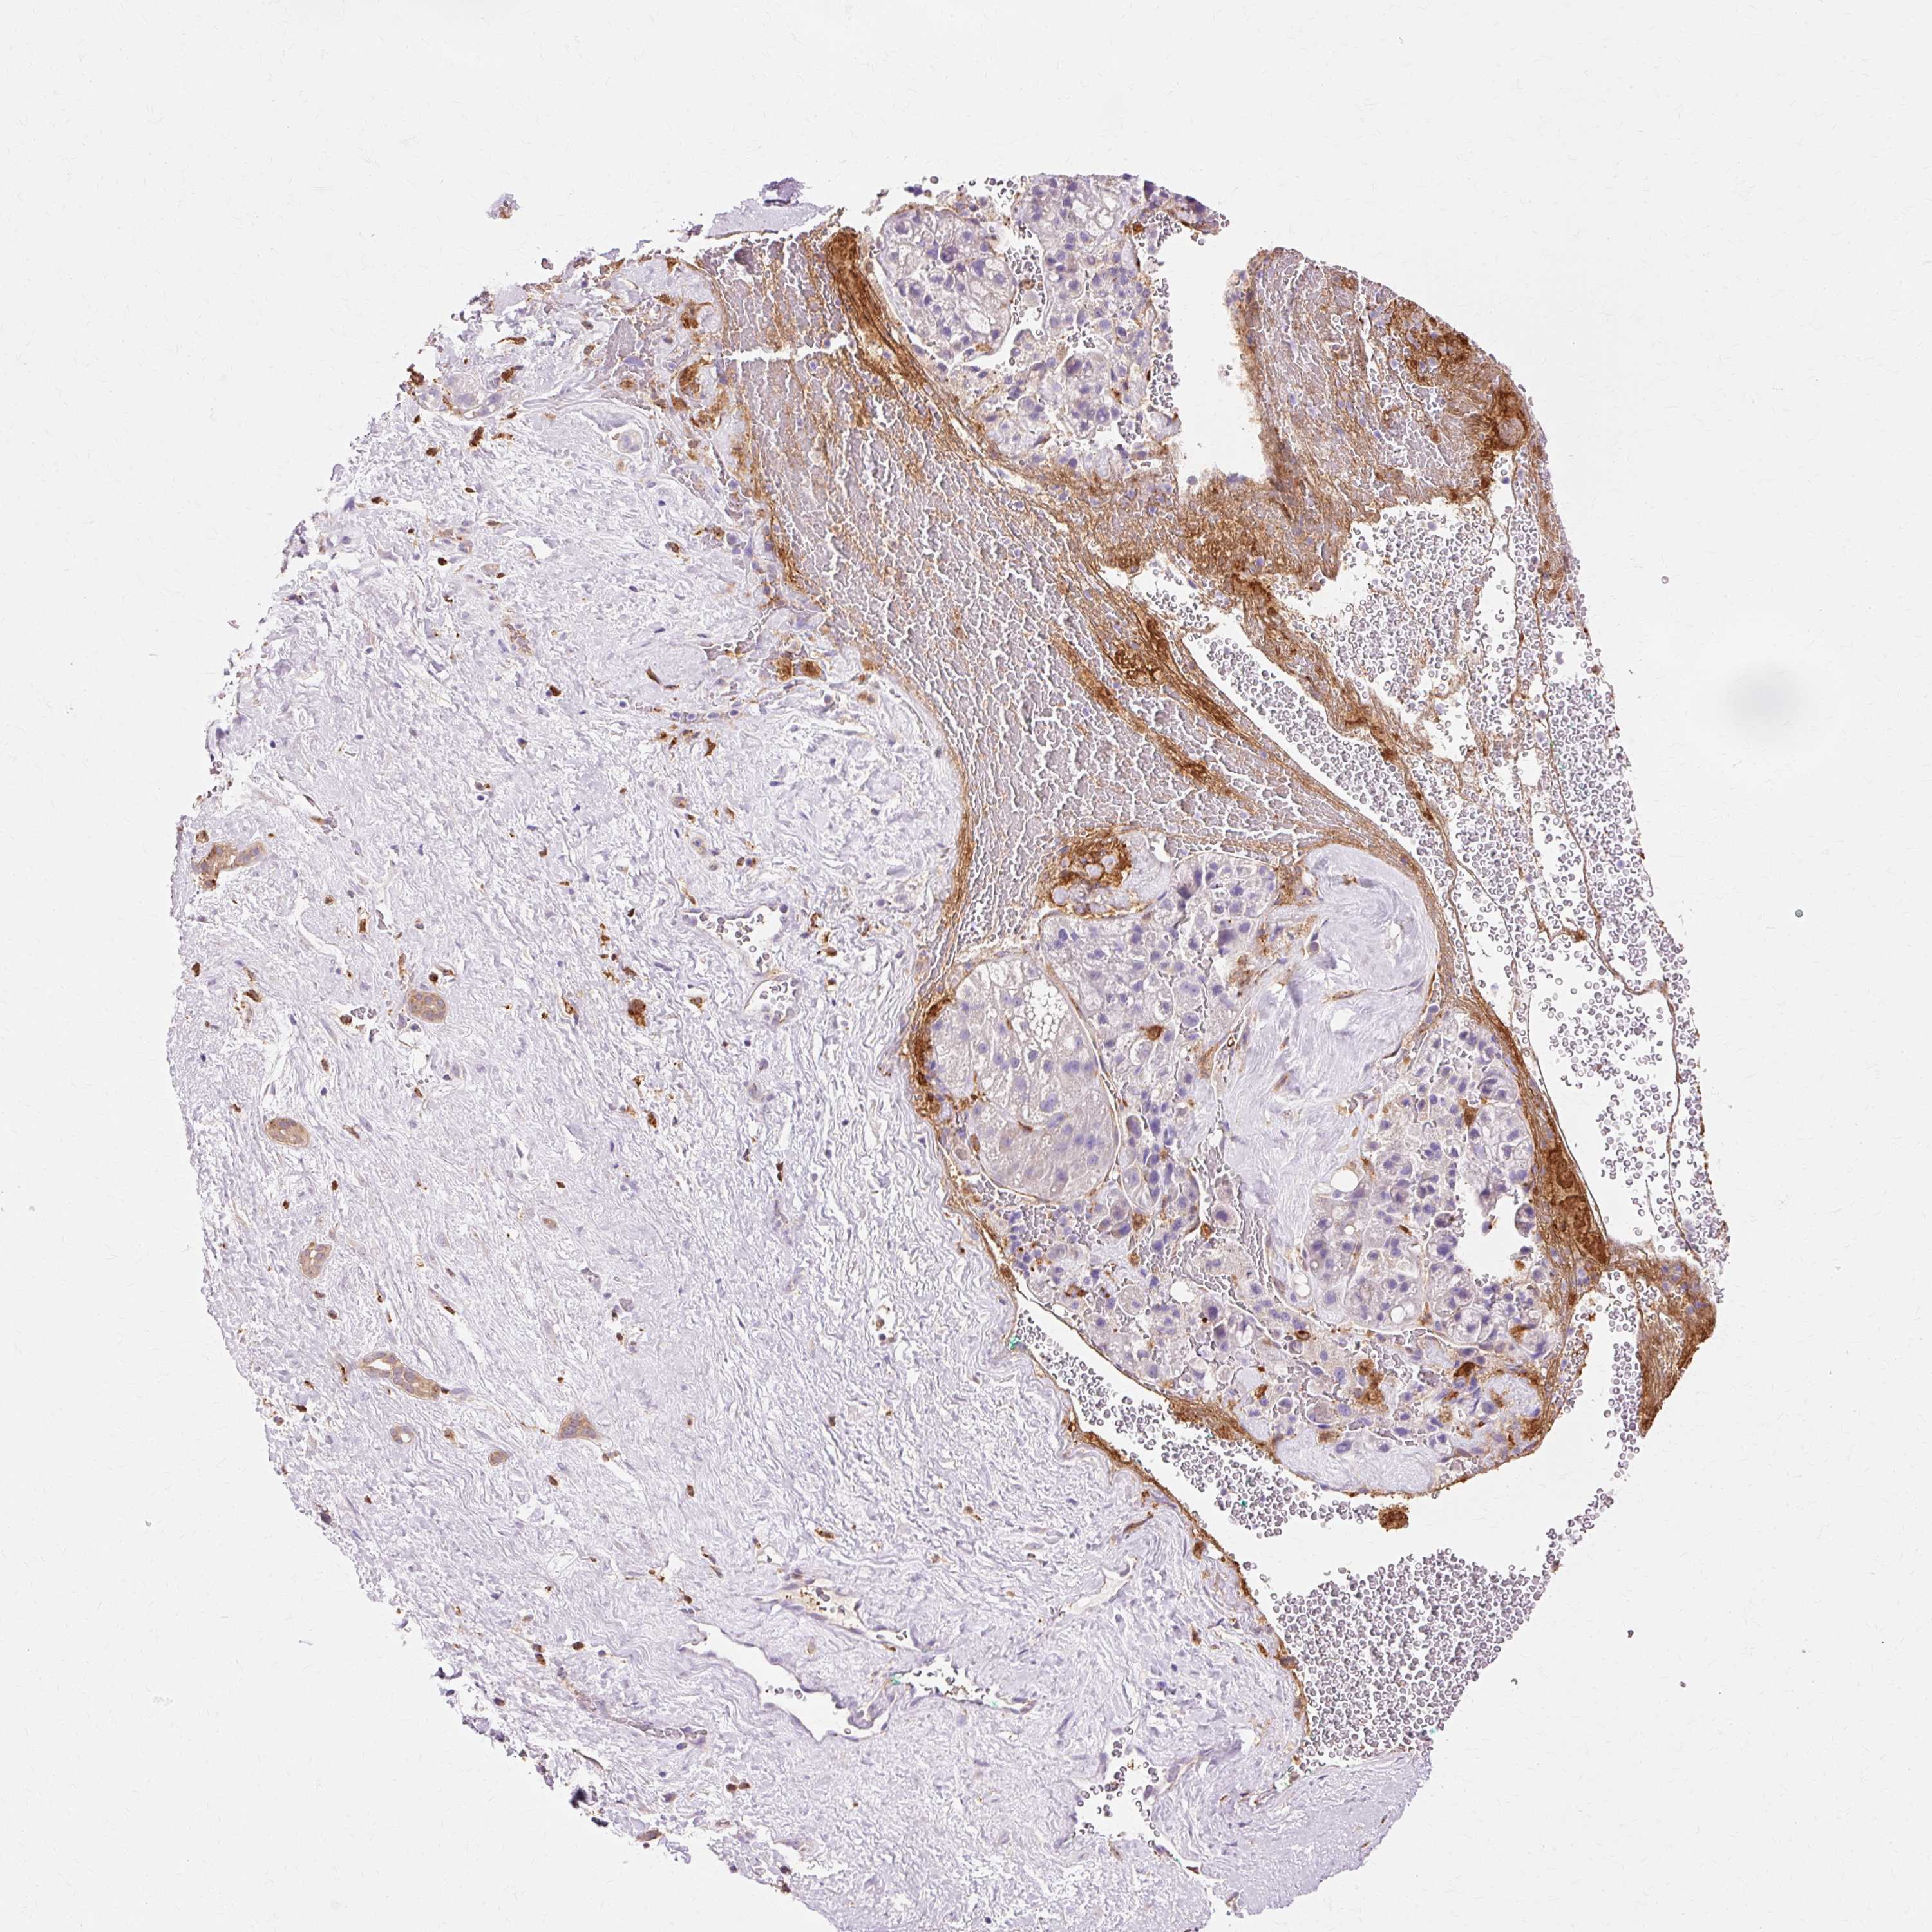

LIVER CANCER - Protein expressioni

A mouse-over function shows sample information and annotation data. Click on an image to view it in a full screen mode. Samples can be filtered based on level of antibody staining by selecting one or several of the following categories: high, medium, low and not detected. The assay and annotation is described here.

Note that samples used for immunohistochemistry by the Human Protein Atlas do not correspond to samples in the TCGA dataset.

Antibody stainingi

Antibody staining in the annotated cell types in the current human tissue is reported as not detected, low, medium, or high, based on conventional immunohistochemistry profiling in selected tissues. This score is based on the combination of the staining intensity and fraction of stained cells.

Each image is clickable and will lead to virtual microscopy that enables deeper exploration of all samples and also displays staining intensity scores, fraction scores and subcellular localization as well as patient and tissue information for each sample.

Antibody CAB011582

Cholangiocarcinoma

Carcinoma, Hepatocellular, NOS